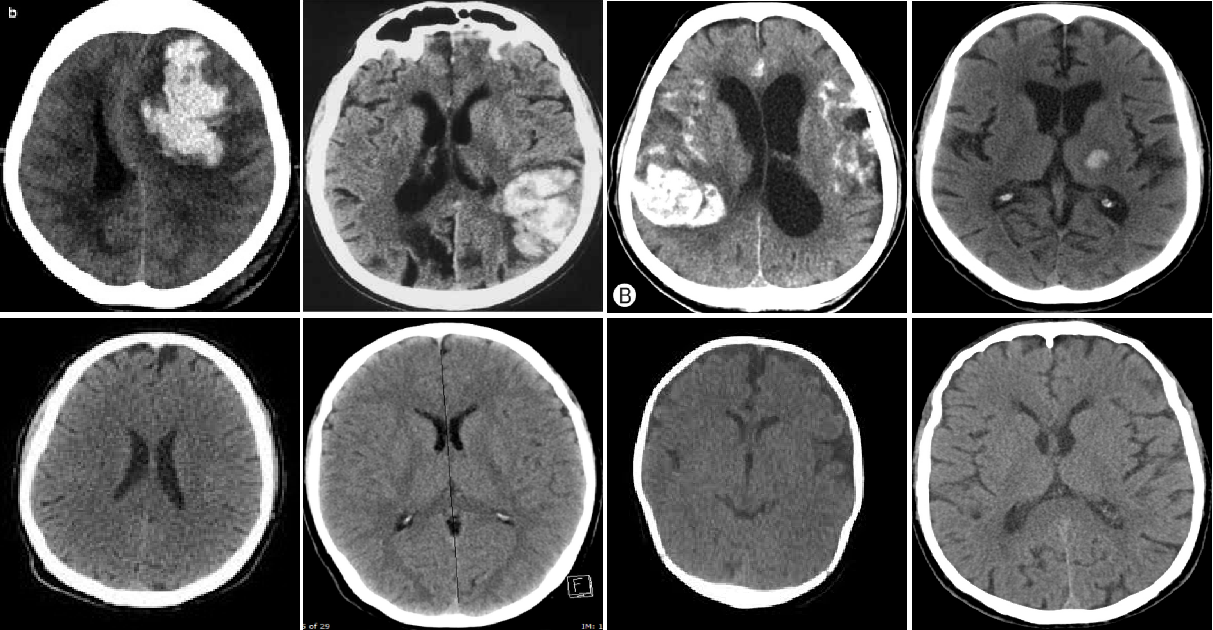

As a further benchmark for our model, we used the Head CT dataset[28], which we selected because of its medical nature and because of its relatively small size, which allowed us to prove the potential of the Vision Transformer architecture even in this particularly challenging type of setting. The head ct dataset is, in fact, composed of a total of 200 images 100 of which represent head ct of healthy individuals while the remaining 100 represent scans of patients with a head hemorrhage. For the purpose of this study, we adopted 80 normal images for the training of the model, while the remaining 120 instances (20 normal, 100 with an hemorrhage) were used in the testing process. Some samples representing normal and anomalous images from the dataset are reported in Fig. 4.1.2.

{figurehere}[Uncaptioned image]

Samples of anomalous (top row) and normal (bottom row) images from the Head CT dataset